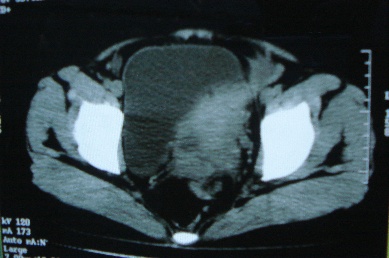

ct10755,女,48岁。感腹胀一周入院。

考虑右侧卵巢囊腺癌并腹腔转移、子宫肌瘤

支持右侧卵巢囊腺癌并腹腔转移

考虑右侧卵巢囊腺癌并腹腔转移可能性大、子宫肌瘤

支持:右侧卵巢囊腺癌并腹腔转移,或囊腺瘤破裂腹腔种植。

支持:右侧卵巢囊腺癌并腹腔转移、腹水、盆腔积液。

考虑为右侧卵巢囊腺癌并腹腔转移、腹水、盆腔积液.

右侧卵巢囊腺癌并腹腔转移,腹水。

支持右侧卵巢囊腺癌并腹腔转移(大量腹水)。